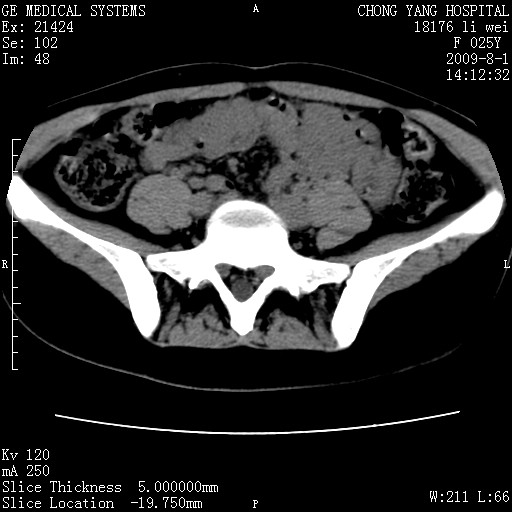

以下是引用pujunzhi在2009-8-1 20:23:00的发言:[br]胸椎旁及背部肌间良性病变,范围广,边界清,沿肌间生长,考虑淋巴管瘤、血管瘤,建议增强扫描。

以下是引用拾荒者在2009-12-30 21:45:00的发言:[br]ct21383:神经纤维瘤病( nf) [br] [br] 神经纤维瘤病。四肢都有,影响美观,四肢上的手术了。[br] [br] [br]谢谢!